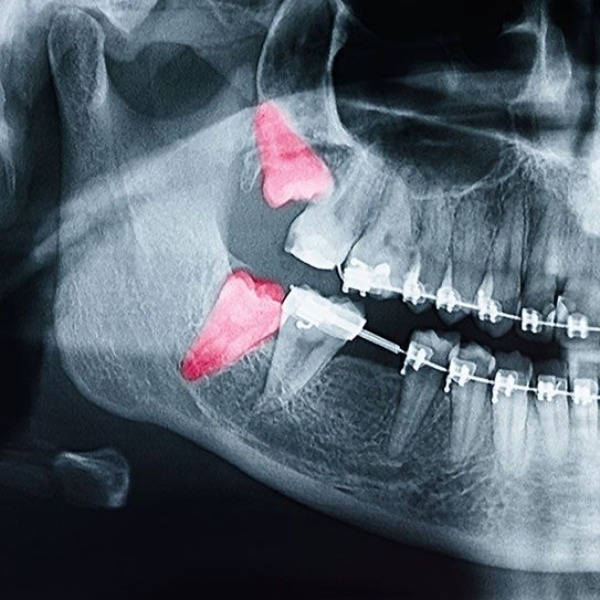

Can Wisdom Teeth Cause Orthodontic Issues? Wisdom teeth, or third molars, usually appear in the late teens or early twenties and often don’t have enough space to grow properly. At Smile Orchid Dental Clinic, Kilpauk, recognized as the Best Dental Clinic in Kilpauk, we often see patients concerned about whether wisdom teeth can cause orthodontic problems. While wisdom teeth don’t always lead to crooked teeth, impacted or partially erupted wisdom teeth can create crowding, discomfort, or pressure on nearby teeth. This can sometimes affect the results of orthodontic treatments like braces or Invisalign if not monitored. Regular dental checkups and X-rays help us detect potential issues early. If needed, timely removal of wisdom teeth can prevent shifting teeth, gum infections, or bite problems. Our experienced dentists use advanced diagnostic tools and gentle techniques to ensure safe and stress-free procedures. Whether you’re experiencing pain, swelling, or want to protect your orthodontic results, our team at Smile Orchid Dental Clinic is here to help. We focus on preventive care and personalised treatment plans to maintain your healthiest smile. Book your consultation today with the Best Dental Clinic in Kilpauk to keep your teeth aligned, healthy, and beautiful for years to come. 📍 Visit Smile Orchid Dental Clinic, Call us now at 07200221777 your trusted dental clinic in Kilpauk, for your Dental care and Confident smile.